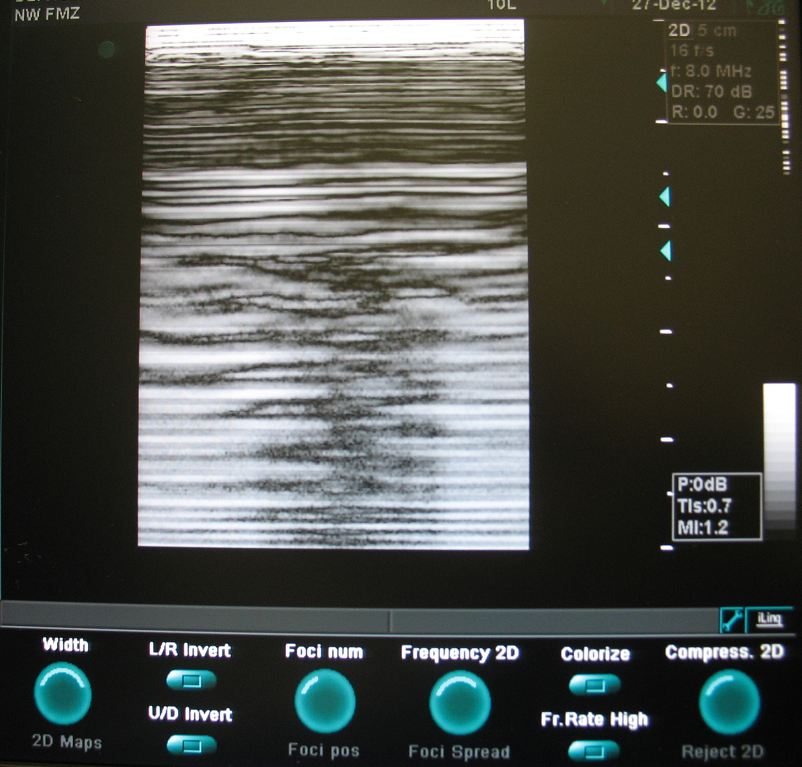

Есть аппарат УЗИ GE Vivid 3 с искажённой картинкой.

Если есть у кого мысли куда копать, просьба поделиться.

Изображение прилагается.

Аппарат очень болен. У него есть как минимум 3 неисправности:

1. После проверки Чек Диском, исправления ошибок и замены нечитаемых секторов, к последнему разделу Swap пропал доступ см. Рис. 1.

2. Тест платы FB, показал, что в одном из каналов завал, и предложил заменить одну из плат TP4 См. рис. 2. Поменял платы местами, результат тот же.

3. Тест платы BF, выдал ошибку цифровых тестов См. рис. 3.

4. В бычном режиме картинка см. рис. 4. Если немного согнуть плату BF, то на изображении пропадают треугольники см. рис. 5, 6. Одновременно при сгибании платы исчезает ошибка АЦП BF см. рис. 7, 8 в след. посте.